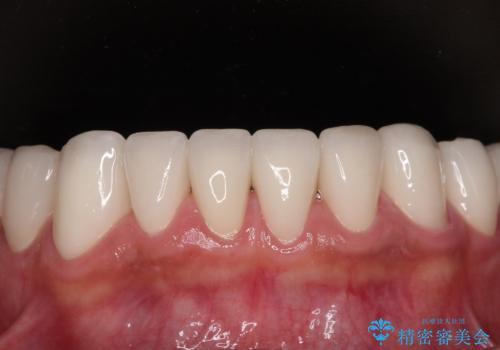

反対咬合を補綴治療で改善すると、上唇へ歯が当たる感覚や、発音時の舌感覚が急激に大きく変化するため、違和感になれるまで時間を要することになります。

仮歯で過ごす期間を一定期間も受けることで徐々に変化になれていくようにし、オールセラミッククラウン装着時には違和感なく過ごすことができるようにしています。